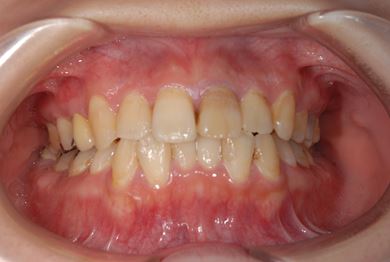

治療前

• 治療前